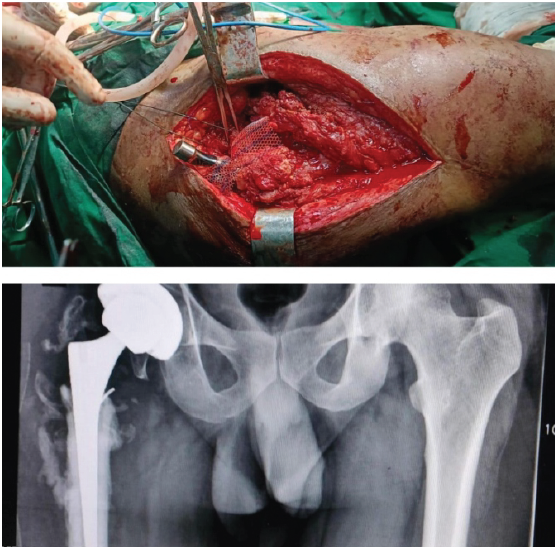

All procedures were performed through the lateral Hardinge approach. The patient was put in the lateral decubitus position. A 15 cm incision was made centered on the greater trochanter, serial dissection was done, and then the acetabulum and femoral preparation were done, and appropriate implants were used. Six patients received uncemented THA, two received cemented THA, and two received hybrid THA [2,7]. Augmentation devices that were commonly used were Prolene mesh (two cases), plate and screws (one case), cerclage wires, and Ethibond sutures were used in selected cases [8]. Prolene mesh was incorporated into the stem (Fig. 1,2) and then the abductor mechanism was reconstructed in a patient with severe lurch and who had undergone multiple procedures(Fig. 1) prior to this, and the patient was put in a derotation boot [8].

Figure 1: Case 1- Diagnosis: Non-union right intertrochanteric femur with severe bone loss and implant in situ. Procedure: Hybrid total hip arthroplasty with meshplasty.